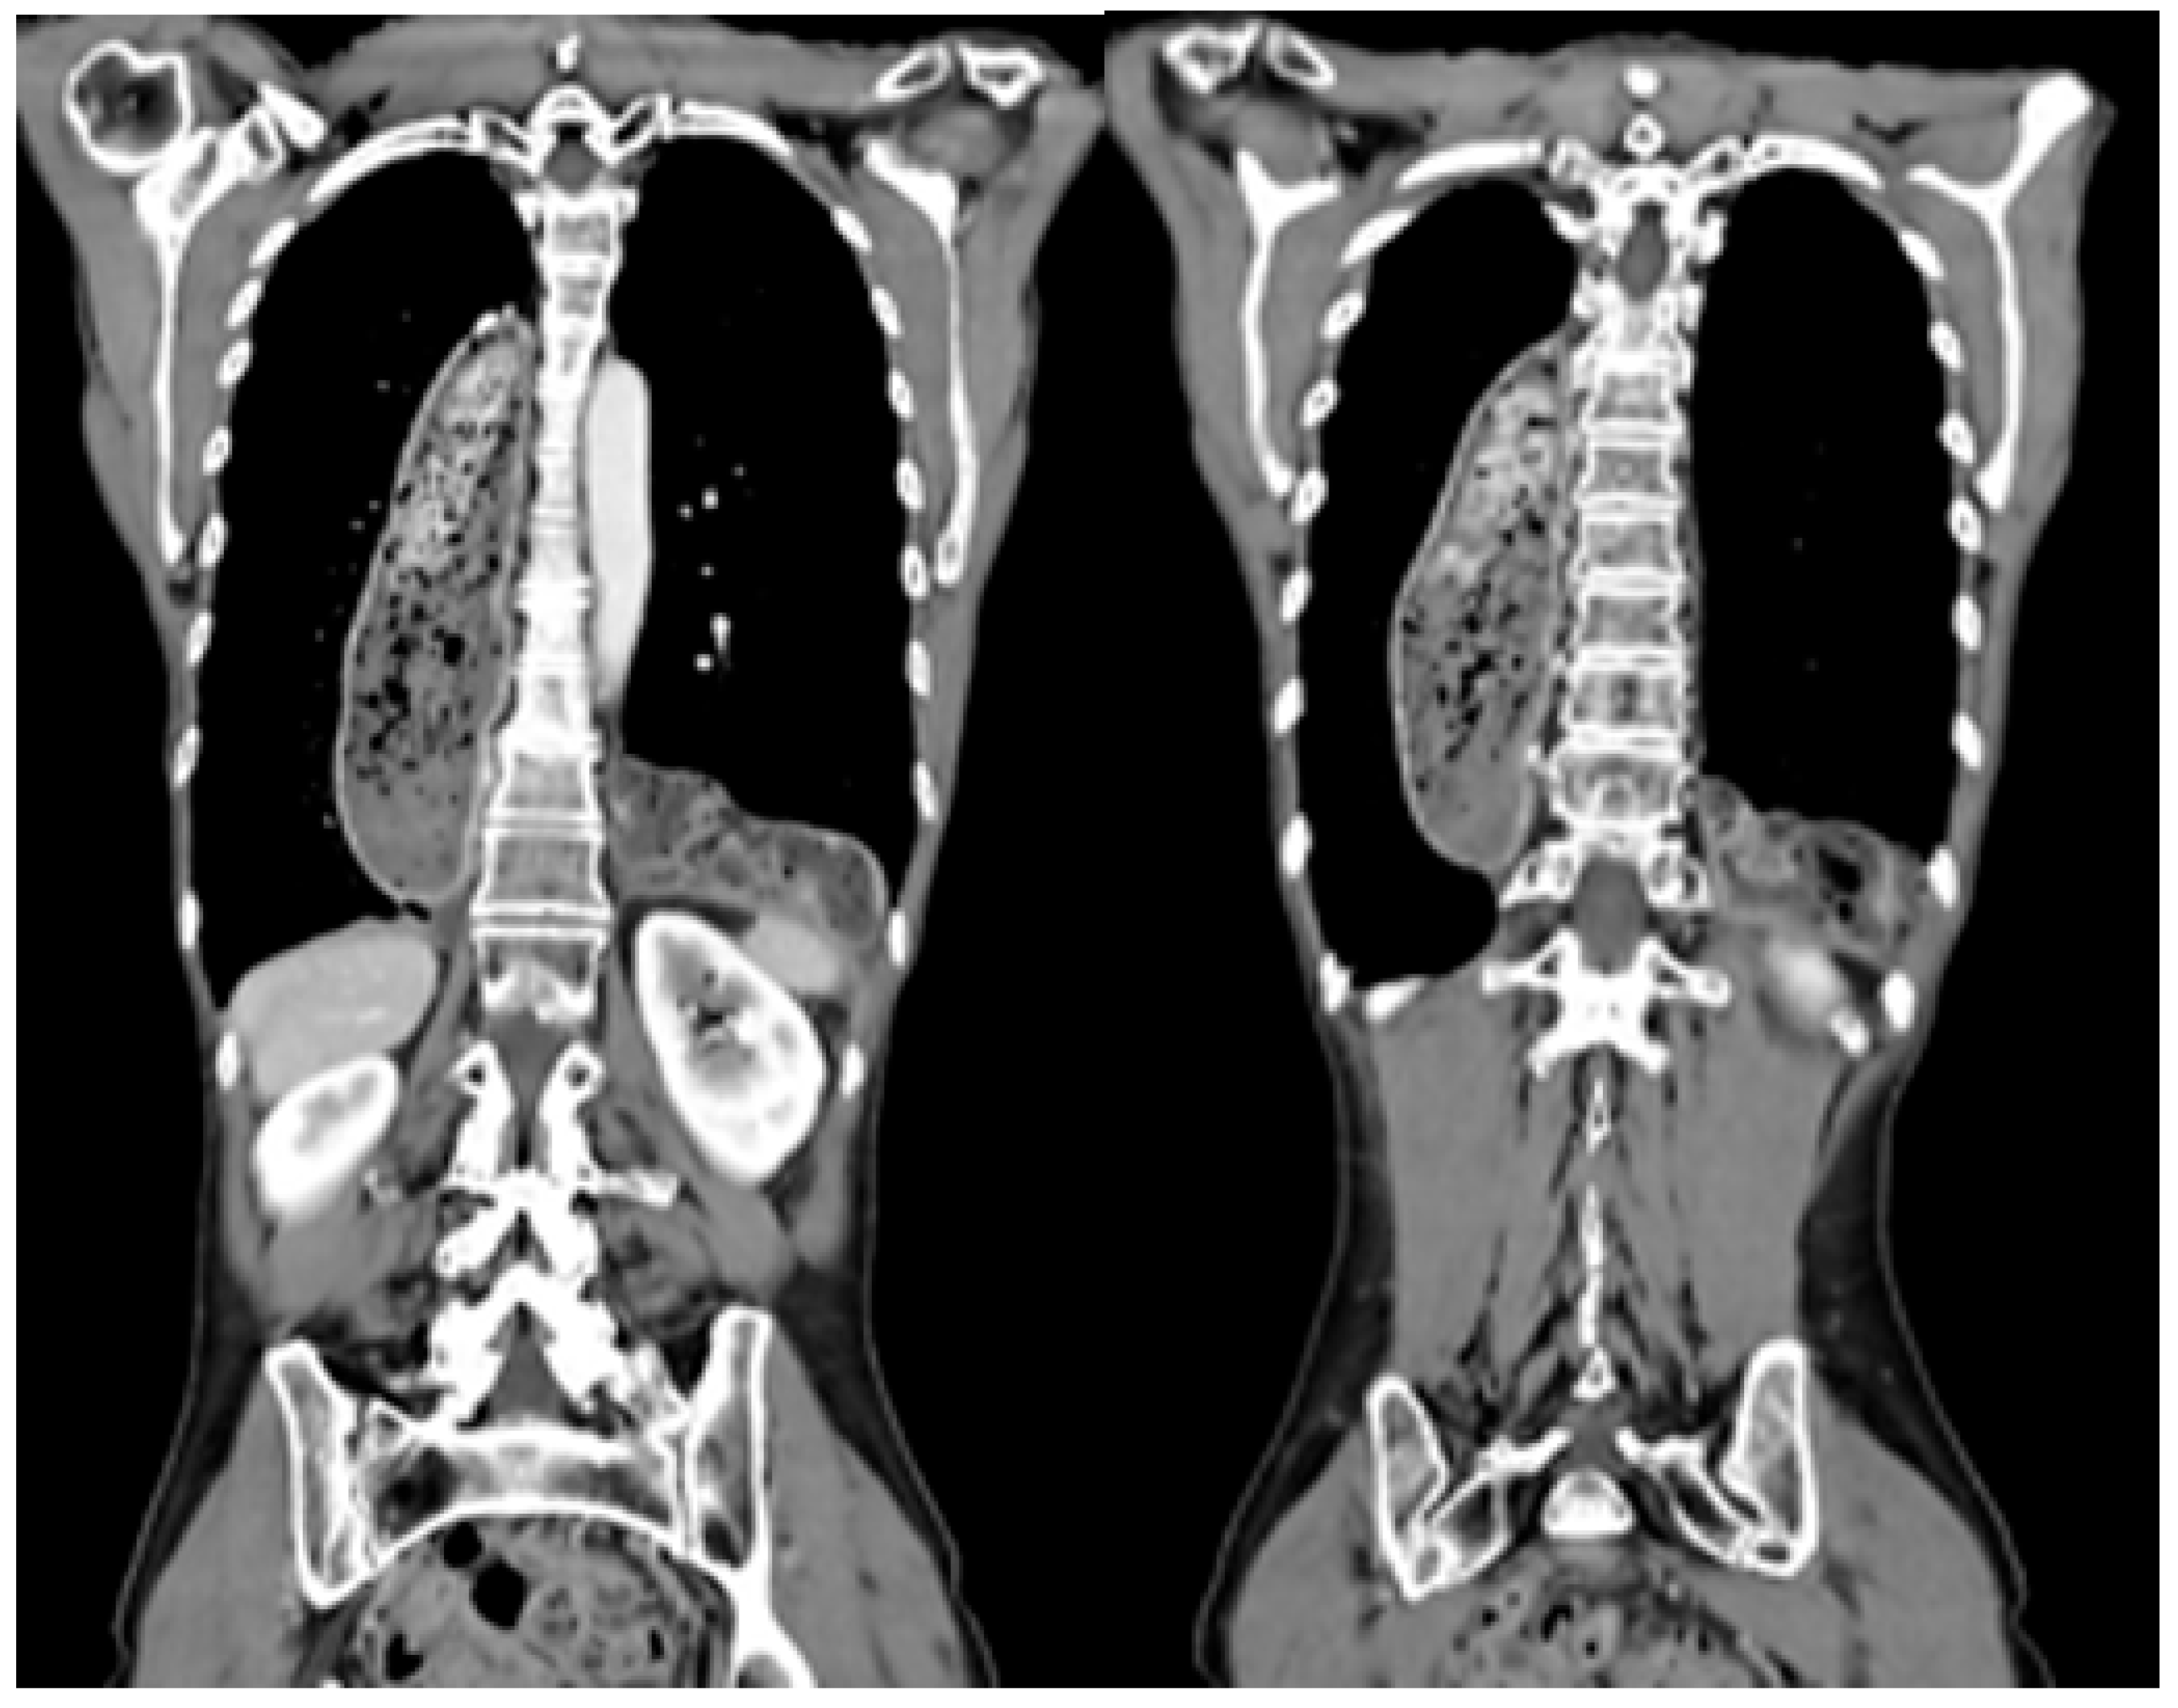

| Localization | |

| Left hemithorax | 7 (36.64%) |

| Right hemithorax | 1 (9.09%) |

| Bilateral | 3 (27.27%) |

| Prolapsed organs | |

| Colon | 10 (90.91%) |

| Small intestine, colon, pancreas, greater omentum | 1 (9.09%) |